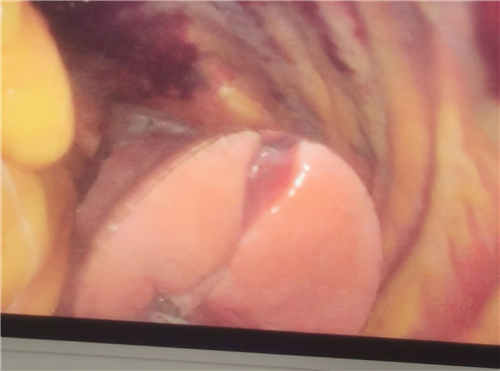

面对这一生命危在旦夕的紧急状况,科主任张秋成迅速集结治疗团队,综合评估患者病情,决定紧急施行“腹腔镜探查+膈肌修补”手术,备选中转开腹方案,确保万无一失。在详尽告知患者及其家属手术风险及可能并发症后,获得全力配合。手术中,团队发现左侧膈肌、心包及胸膜腔破裂,胃与大网膜疝入胸腔,左肺完全压缩。经过精细操作,成功将疝入器官复位,修复破裂部位,手术出血量极少,患者生命体征平稳,顺利返回病房。